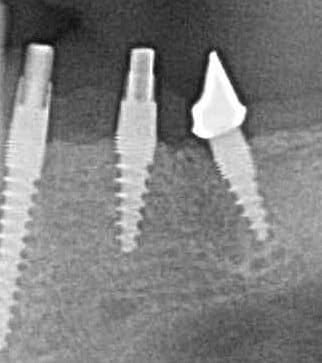

Pour ceux que ca interessent, et parce qu on a m a demandé des cas supplémentaires dans le sujet 23 implants rehabilitation totale, voici un autre cas d implantation immédiate avec la technique minimalement invasive et condensation grace aux forets.

Le patient a reçu un traitement il y a dix ans dans le maxillaire et dans le 4eme quadrant.Comme on peut le voir j´ai du extraire quelques dents au maxillaire: 35 37 et 45.

Le septum de la 37 a été foré avec un foret conique 3 faces.

J ai planté à 60 Ncm sans fracturer le septum.Juste après l opération , les prep caps en zircon ont été cémenté.La restauration définitive 34 jusqu` à 37 été fixé 2 semaines après l implantation avec implantlink (detax). Après un an, le bridge a été retiré facilement pour voir l´état de la gencive et faire une radio de contrôle.On la re ossifiction est satisfaisante et que la gencive "aime" le zircon.

Le bridge a ensuite été recémenté sans correction nécessaire du bridge.